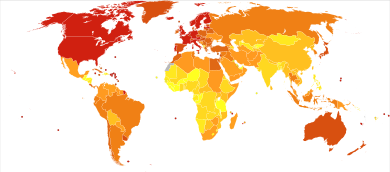

| Micrograph of a plasmacytoma. H&E stain | |

ورم نقوي متعدد إنگليزية: Multiple Myeloma هو مرض سرطاني يصيب الخلايا البلازمية من نوع B مما يؤدي إلى تكاثر هذه الخلايا بشكل غير طبيعي و تكدسها في نخاع العظم. يشكل ما نسبته 1% من الأمراض السرطانية بشكل عام و 10% من الأصابات بسرطان الدم. معدل عمر المريض عند تشخيص المرض يتراوح مابين 60-65 عاما. ينتشر المرض بين الأشخاص ذوي الأصول الإفريقية أكثر من البيض و الآسيويون.